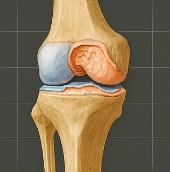

무릎 연골 손상 증상 무릎 연골 손상이란 무엇인가?

무릎 연골은 대퇴골(허벅지뼈)과 경골(정강이뼈) 사이에 존재하며, 충격을 흡수하고 관절을 부드럽게 움직이게 도와줍니다. 연골이 마모되거나 찢어지면 관절 간 마찰이 심해지고, 염증과 통증이 발생합니다. 대표적인 형태는 다음과 같습니다.

- 반월상연골 손상: 무릎 중앙의 C자 형태 연골이 찢어짐

- 연골연화증: 무릎 연골이 말랑해지며 기능 저하

- 연골 마모: 반복적 충격으로 연골이 닳아 없어짐